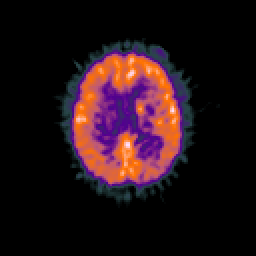

Glioma overlay -- Slice #73

[Home][Help][Clinical] Slice 73